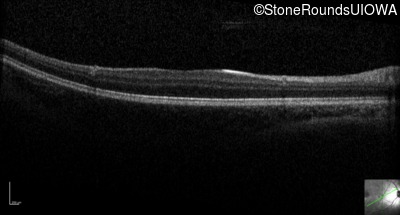

Optical Coherence Tomography - Left - 20/63 -2

Exemplar / OCT Stack

OCT Stack